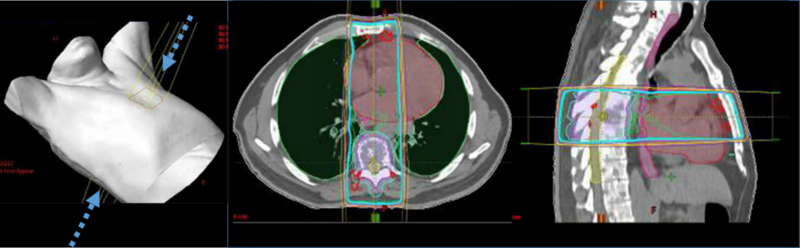

Traditional conventional radiotherapy techniques (either 2D or 3D conformal radiotherapy) have been used in patients with osseous metastatic disease, including spine metastases (Fig. 1). Stereotactic radiosurgery (SRS) techniques, initially developed for patients with intracranial metastasis, have increasingly been tested in patients with spine metastasis with encouraging results (Fig. 2).

Figure 1